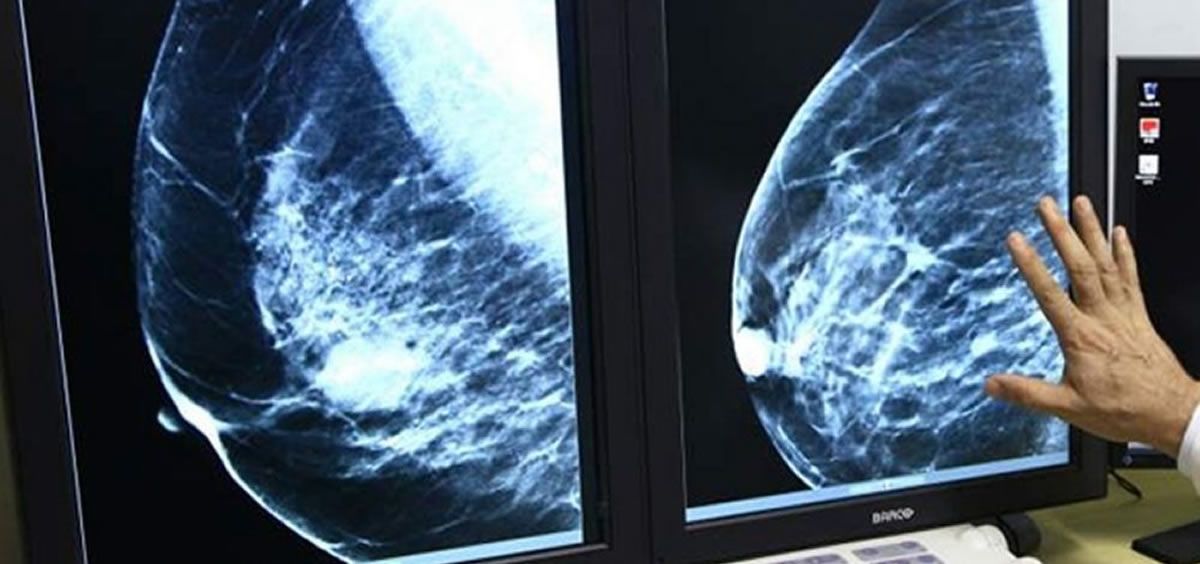

El ensayo puso a prueba la seguridad y eficacia del fármaco en personas con cáncer de mama HER2 positivo con metástasis, un subtipo muy agresivo que afecta hasta al 20% de las pacientes. Su nombre se debe la proteína HER2 que expresan estas células cancerosas y que acelera el desarrollo del tumor.

El fármaco funciona como un caballo de Troya: uno de los compuestos (trastuzumab) se adhiere a las células cancerosas mediante la proteína HER2 y libera en ellas un compuesto quimioterápico (deruxtecan). De ese modo, se destruyen las células malignas mientras se evita dañar a las sanas.